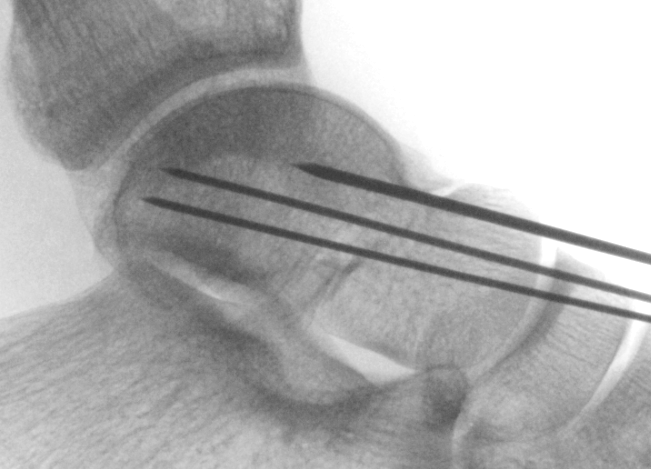

Cannulated screws

Xrays

| AP | Lateral | Canale View |

|---|---|---|

| Entry point of the screws |

Evaluate neck reduction

|

Evaluates the neck reduction |

Lateral off articular surface Medial through articular cartilage |

Depth of screws |

Beam angled 75o to foot Foot 15o pronated |

1. Retrograde (anterior to posterior) into posterior talus body

A. Lateral screw

- insert proximal to articular surface of head on lateral side

- bone is very curved here

- can lag screw as usually no comminution

B. Medial side

- insert through articular surface

- countersunk screws through articular surface

- avoid lag screw techniques medially as may compress comminution into varus

AP, Canale and Lateral xray

Retrograde screws